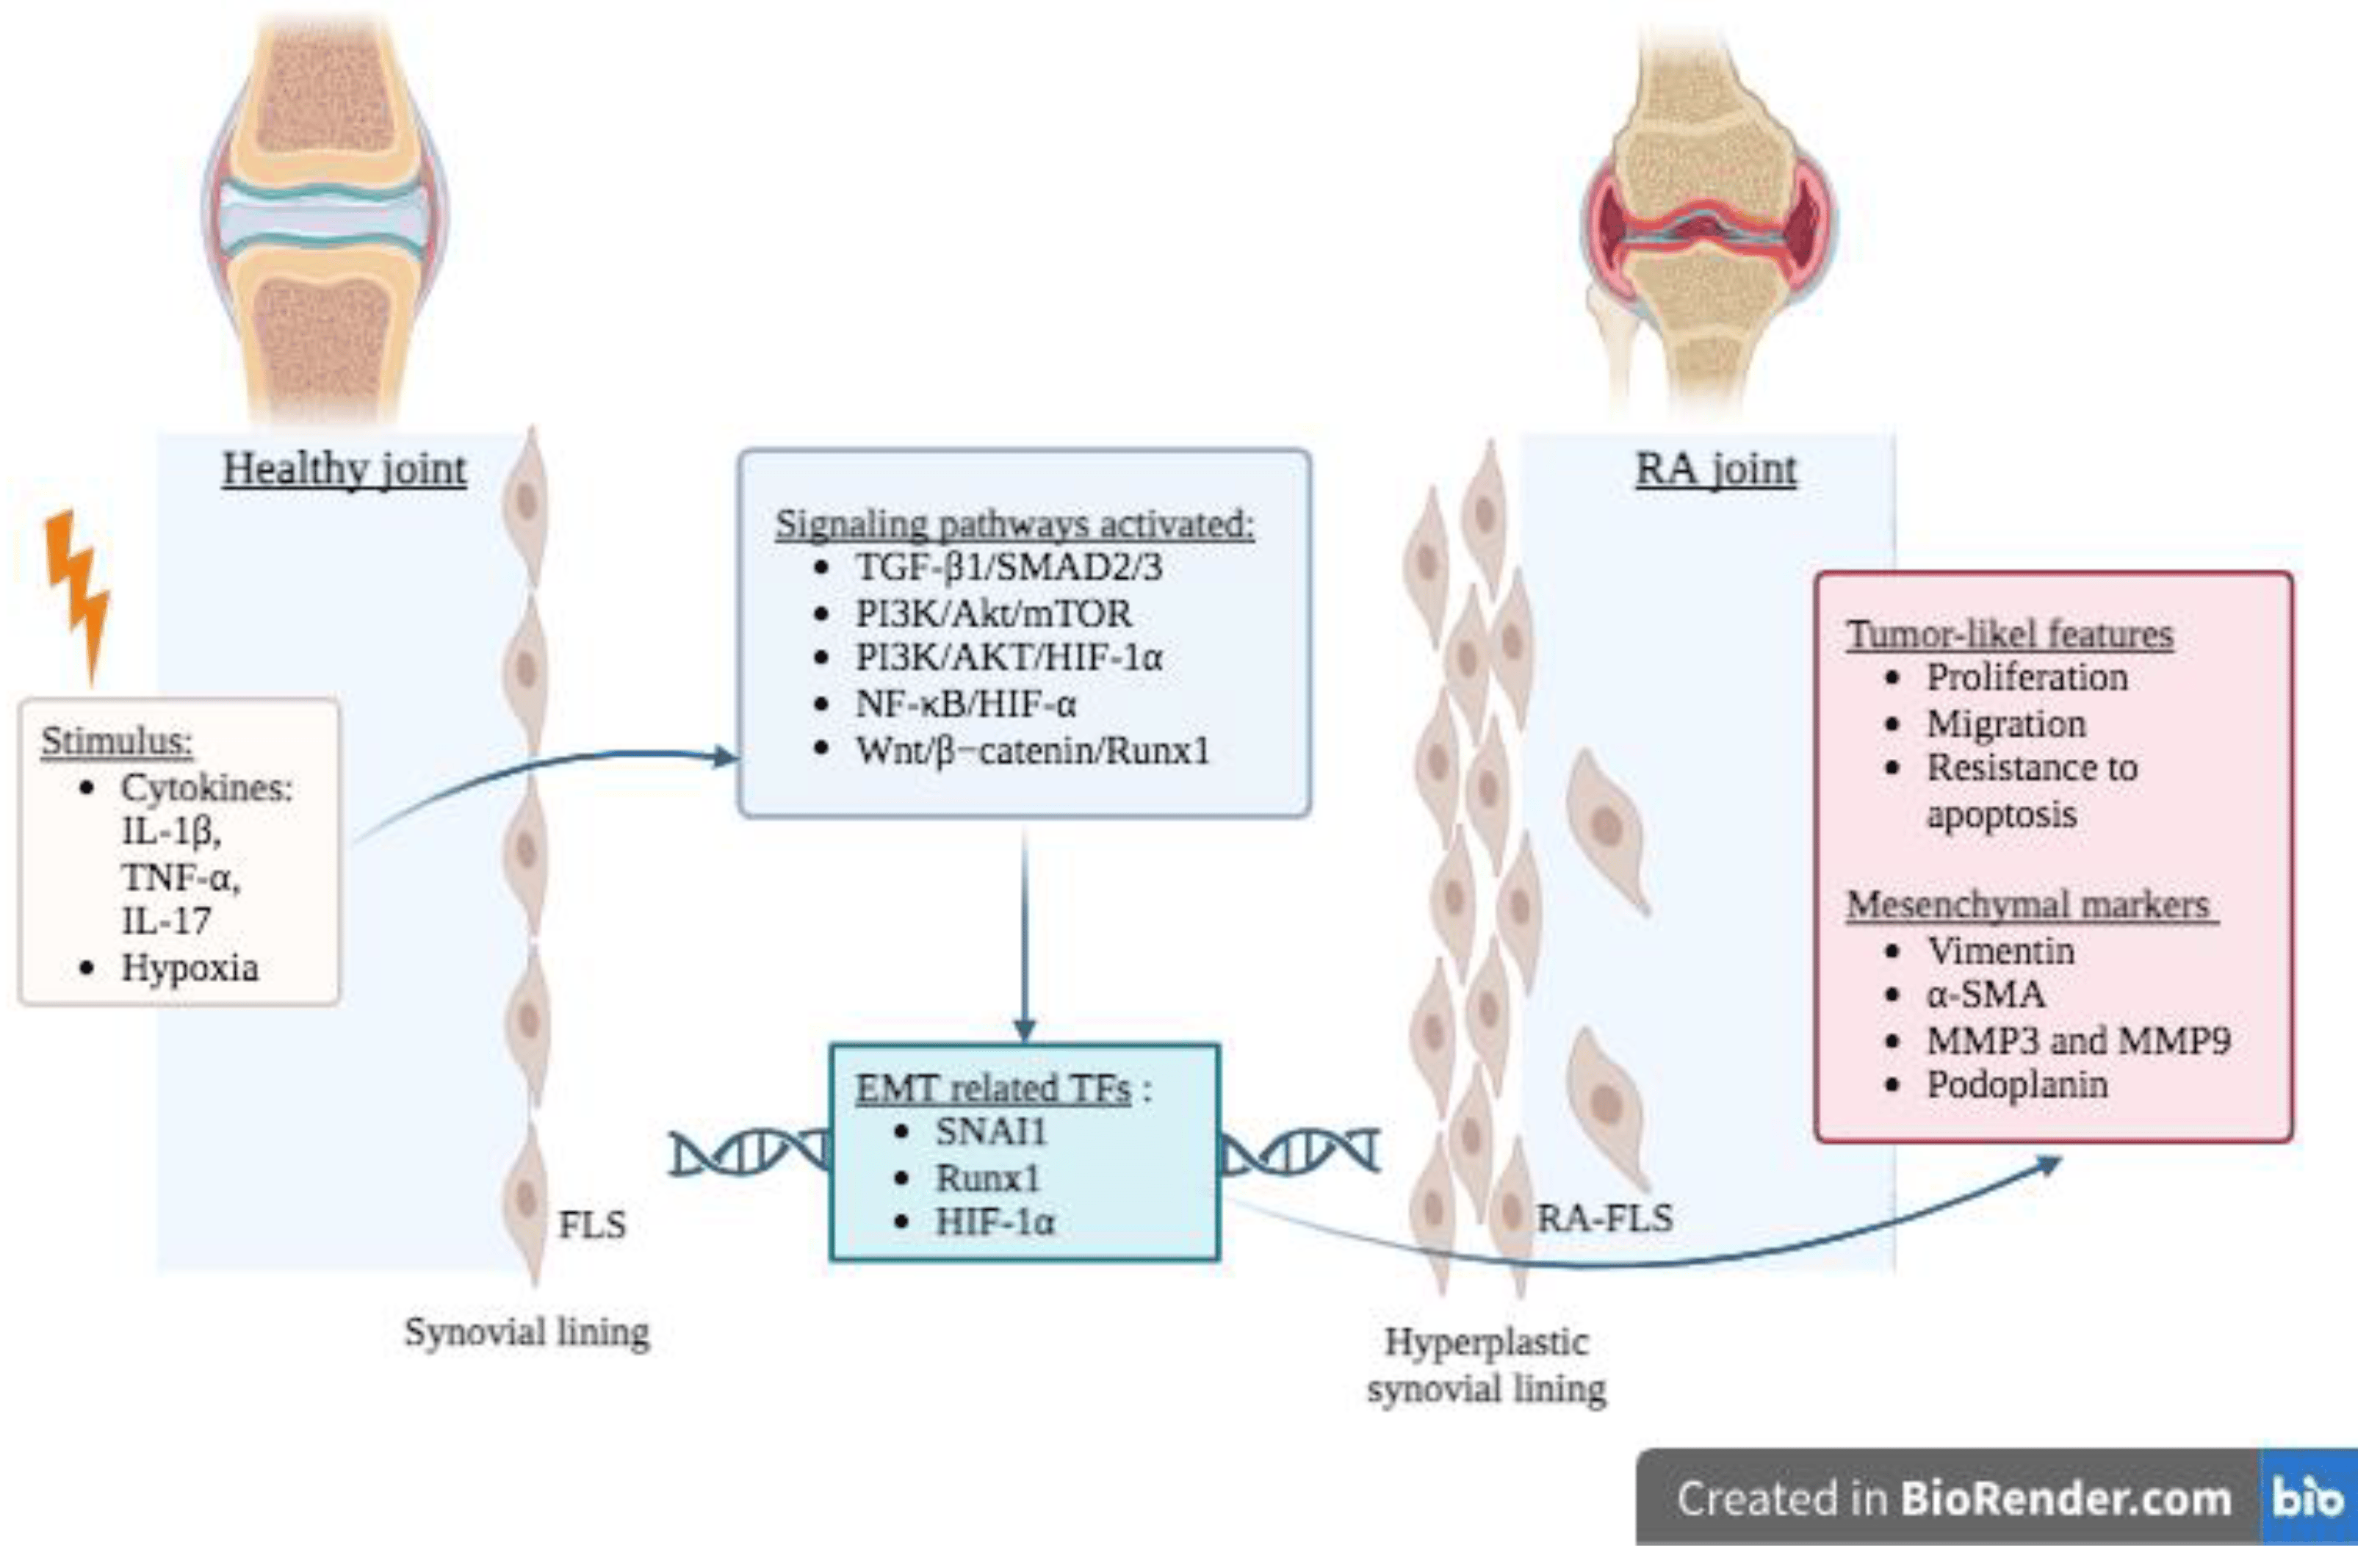

Arthritic changes – Arthritis is related to a condition of painful joints due to inflammation or swelling. A type of arthritis is rheumatoid arthritis, it is an autoimmune disease where the immune system attacks the joints, starting with the lining of joints. Rheumatoid arthritis is heavily related to lung problems, about 80% of arthritic patients have lung-related issues, making it the second leading cause of death with rheumatoid arthritis patients. Rheumatoid arthritis caused lung problems are most commonly extra-articular i.e., outside of the joints and involves pulmonary nodules; damage to the lung airways, pleural effusion and interstitial lung disease. In rheumatoid arthritis associated interstitial lung disease the auto-immune system gets over active and attacks the lungs and causes scarring. With time, the scarring build-up leads to difficulty breathing and reduced lung function.